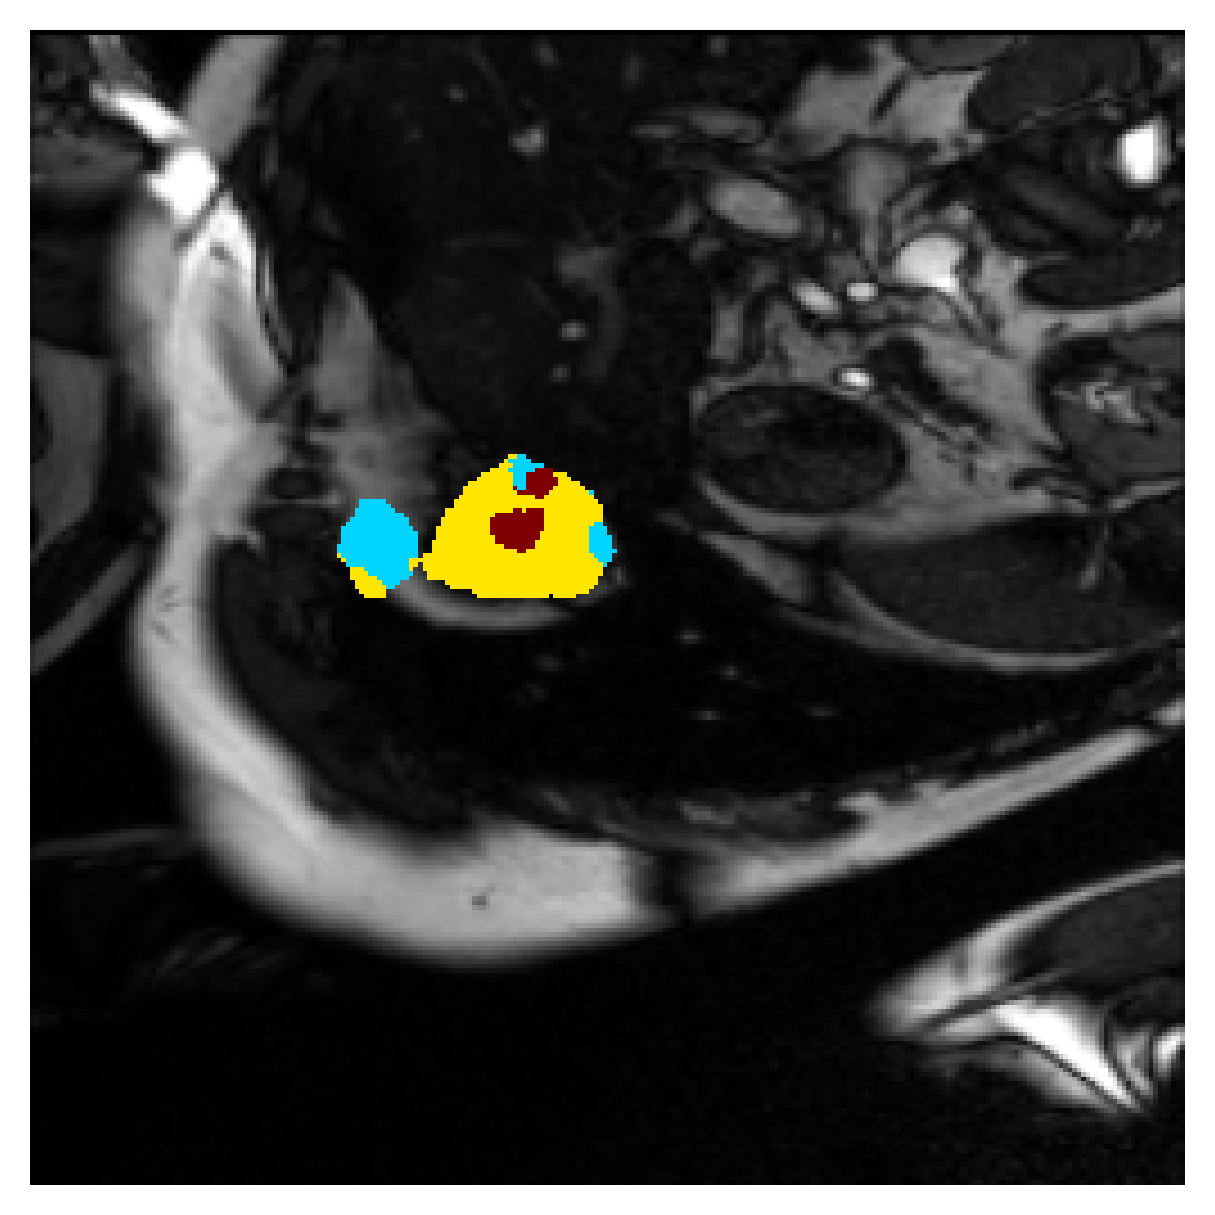

Qualitative comparison

| (a) Ground truth | (b) , full | (c) , weak | (d) |

| (full) | supervision | supervision | |

| (e) | (f) | (g) | (h) CRF-loss |

In Figure 6 we provide qualitative results on a number of randomly chosen test set slices. Upon visual inspection, we can observe that training with the intensity-aware distances (particularly with and ) follows the image gradients better and is better at recovering the underlying shape than the Euclidean version. The CRF-loss seems to recover the shape of the myocardium and left ventricle to some extent, but fails entirely on the right ventricle.